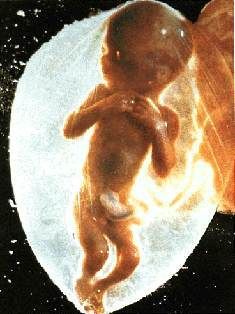

La gravidanza procede bene ed ormai siamo veramente agli sgoccioli. Girovagando per internet guardate cos'ho trovato....incredibile....è veramente il MIRACOLO DELLA VITA

La gravidanza procede bene ed ormai siamo veramente agli sgoccioli. Girovagando per internet guardate cos'ho trovato....incredibile....è veramente il MIRACOLO DELLA VITA